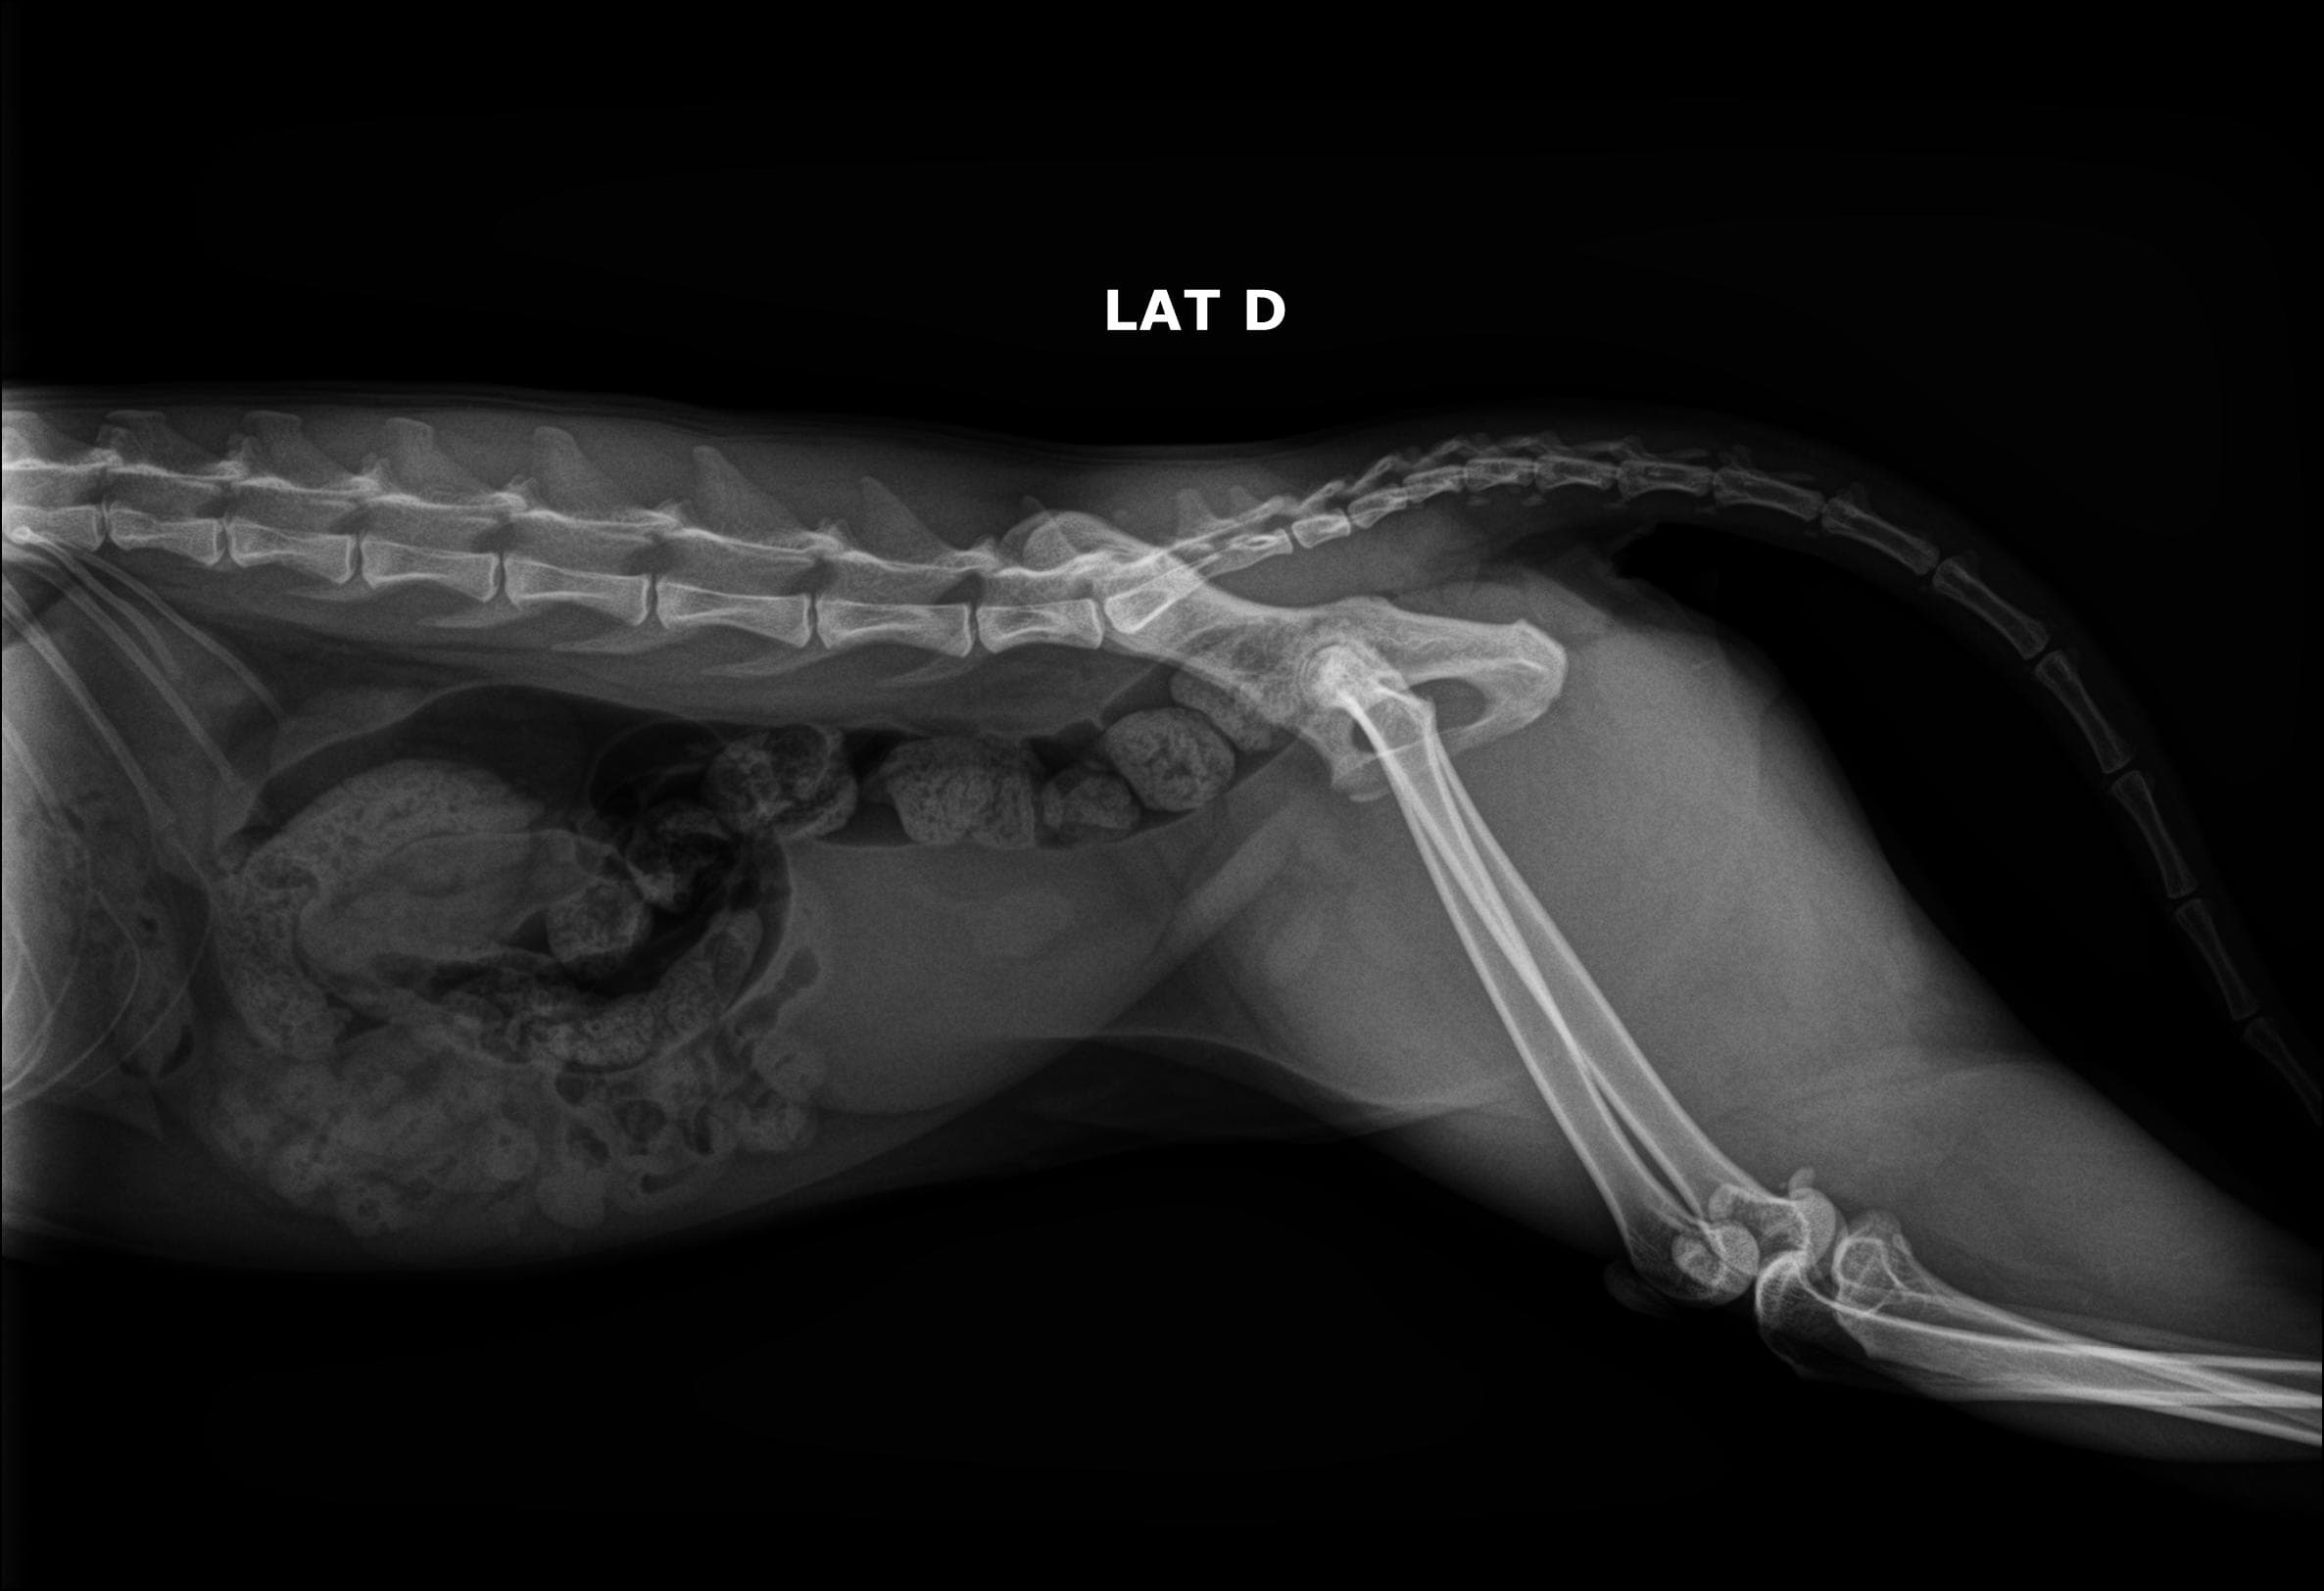

Nosso serviço de radiologia digital é projetado para oferecer diagnósticos precisos para cuidar da saúde dos pets. Contamos com equipamentos de última geração que nos permitem capturar imagens de alta qualidade e definição, fornecendo uma visão clara das estruturas. Essa tecnologia avançada nos permite identificar diversas condições médicas com maior precisão e detalhamento.